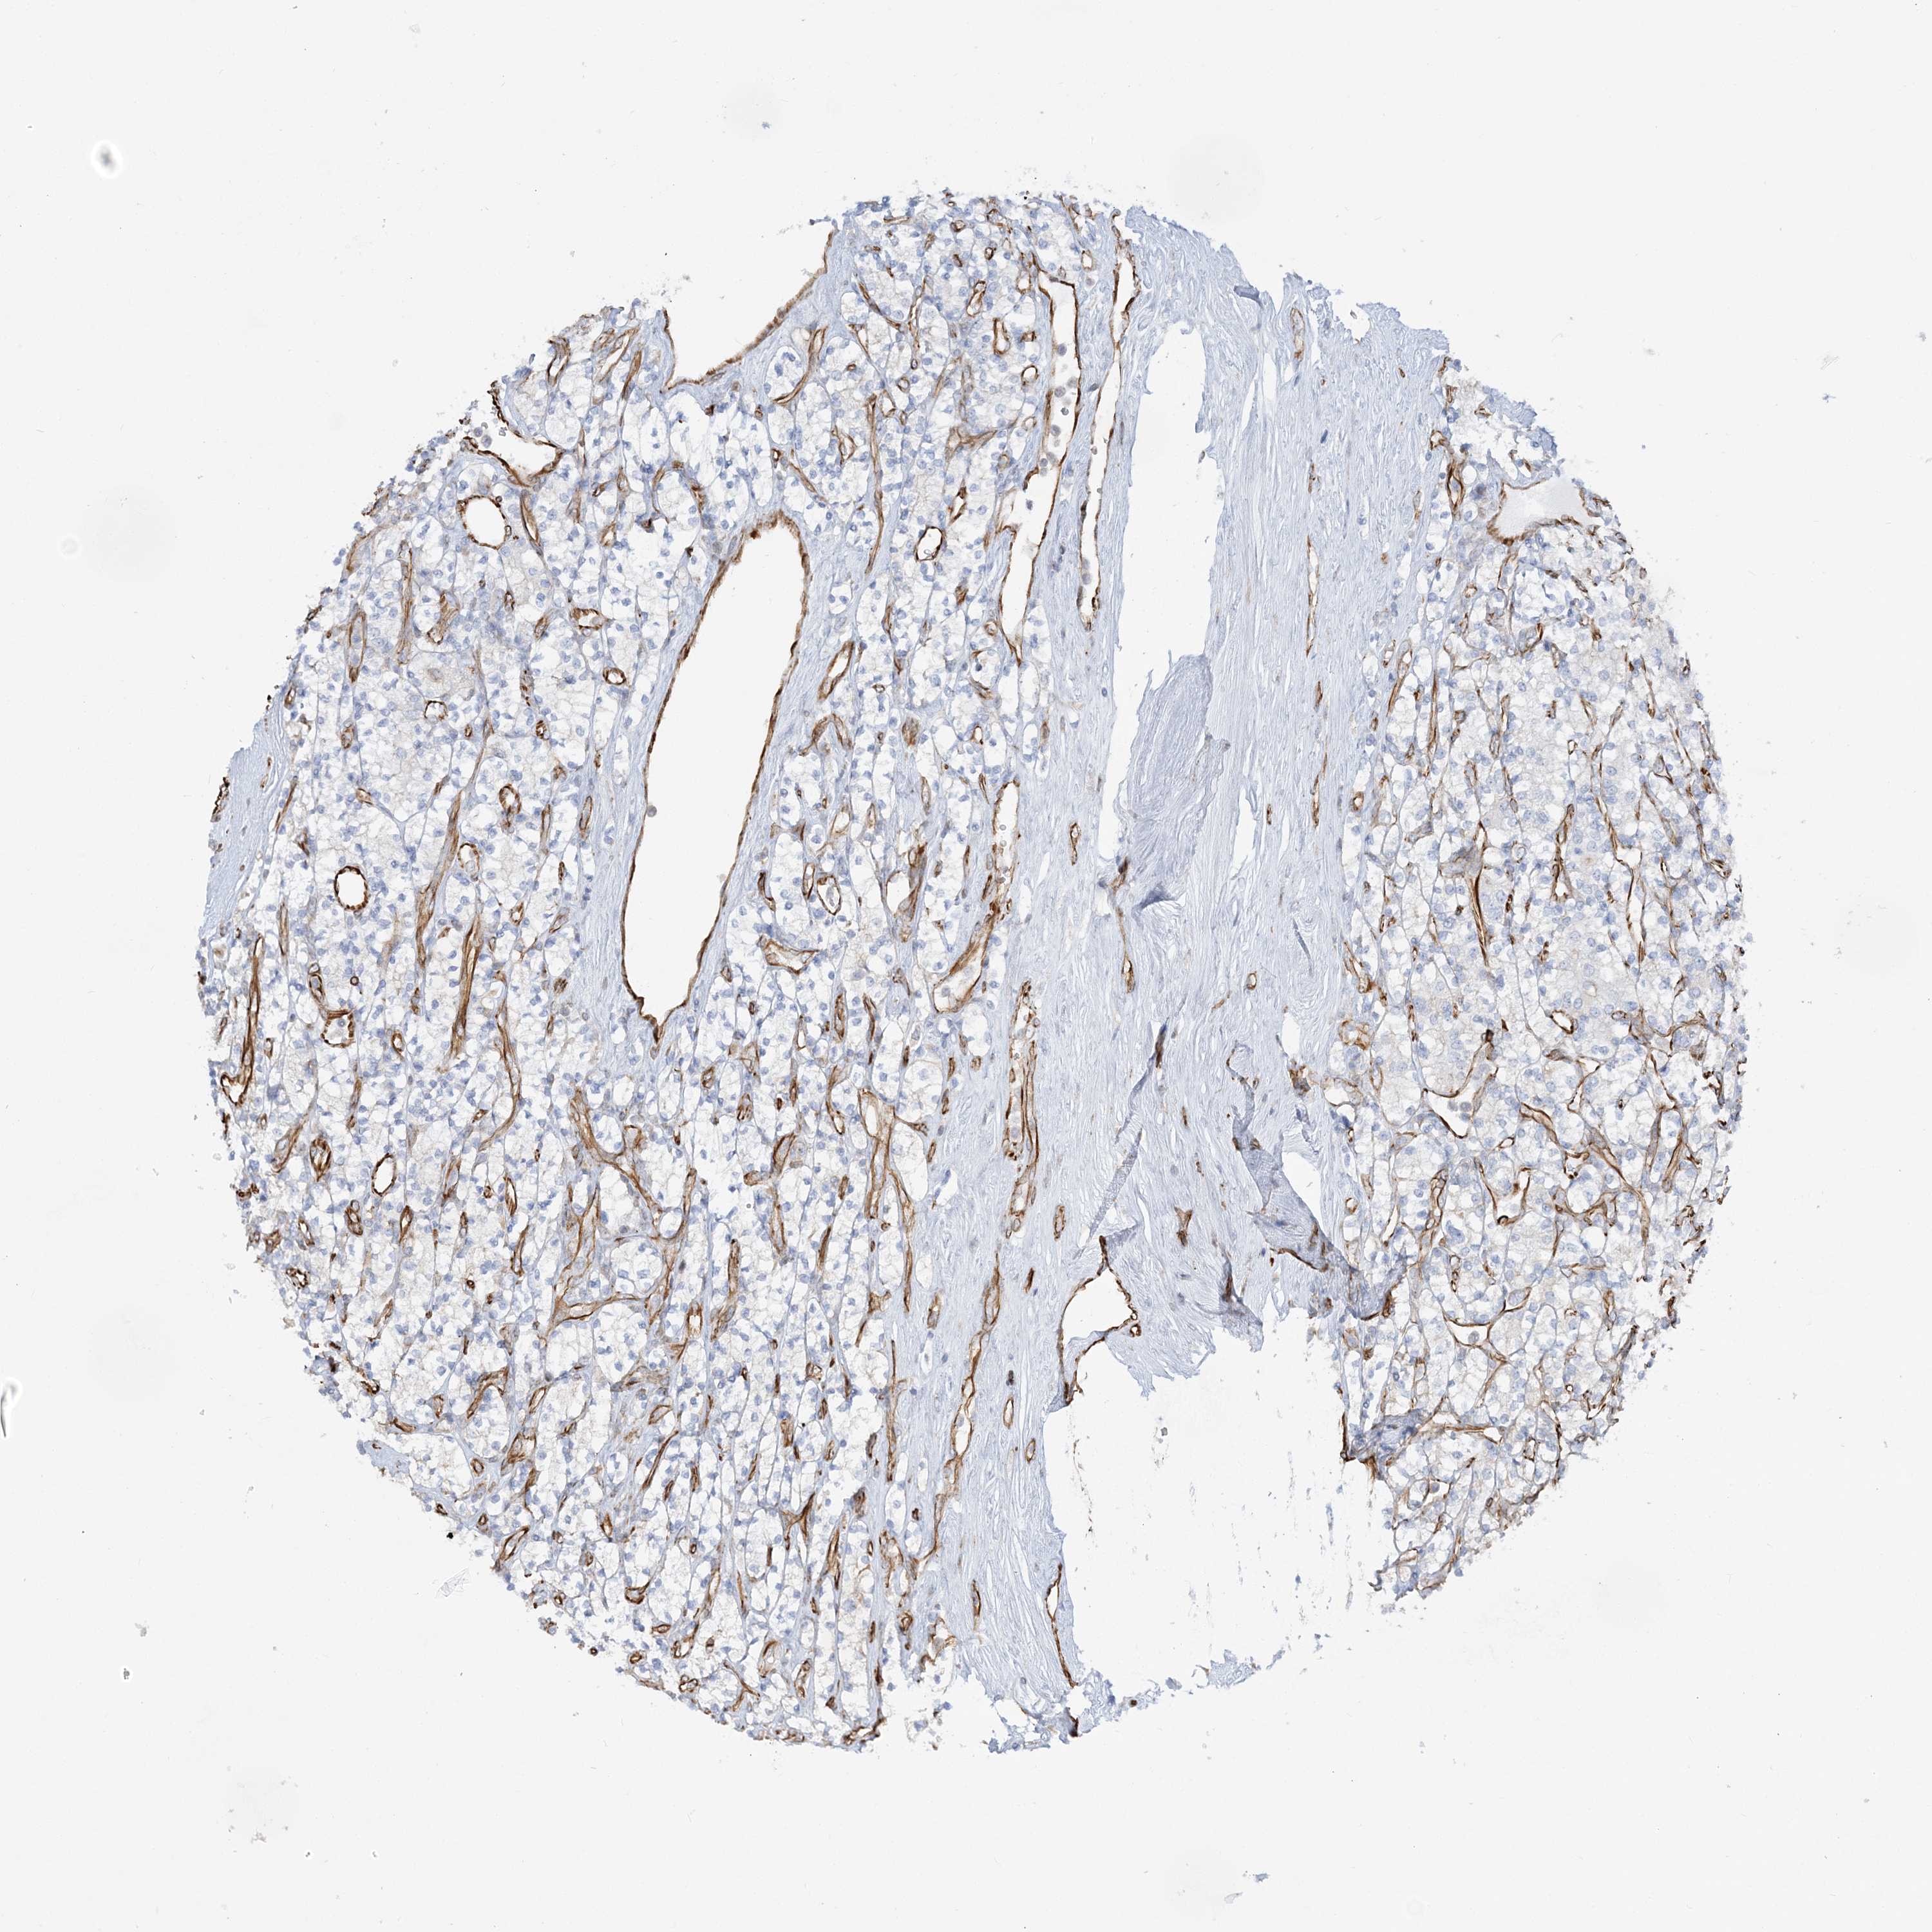

KIDNEY RENAL CLEAR CELL CARCINOMA (VALIDATION) - Interactive survival scatter ploti

The Survival Scatter plot shows the clinical status (i.e. dead or alive) for all individuals in the patient cohort, based on the same data that underlies the corresponding Kaplan-Meier plots. Patients that are alive at last time for follow-up are shown in blue and patients who have died during the study are shown in red.

The x-axis shows the expression levels (FPKM) of the investigated gene in the tumor tissue at the time of diagnosis. The y-axis shows the follow-up time after diagnosis (years). Both axes are complimented with kernel density curves demonstrating the data density over the axes. The top density plot shows the expression levels (FPKM) distribution among dead (red) and alive patients (blue). The right density plot shows the data density of the survived years of dead patients with high and low expression levels respectively, stratified using the cutoff indicated by the vertical dashed line through the Survival Scatter plot. This cutoff is automatically defined based on the FPKM cutoff that minimizes the p-score. The cutoff can be changed by dragging the vertical line or by entering a cutoff value in the square labeled "Current cut-off".

Under the Survival Scatter plot the p-score landscape (black curve; left axis) is shown together with dead median separation (red curve; right axis). Dead median separation is the difference in median mRNA expression between patients who have died with high and low expression, respectively. It is calculated as follows: median FPKM expression of dead patients with high expression - median FPKM expression of dead patients with low expression. This is intended to aid the user in visually exploring custom cutoffs and the associated p-scores and dead median separation.

Individual patient data is displayed and can be filtered by clicking on one or more of the category buttons on the top of the page. Categories describing expression level and patient information include: high, low, alive, dead, female, male and tumor stages. The scale of the x-axis can be toggled between linear and log-scale by clicking on the "x log" button. Mouse-over function shows TCGA ID, patient information and mRNA expression (FPKM) for each patient.

& Survival analysisi

Kaplan-Meier plots summarize results from analysis of correlation between mRNA expression level and patient survival. Patients were divided based on level of expression into one of the two groups "low" (under cut off) or "high" (over cut off). X-axis shows time for survival (years) and y-axis shows the probability of survival, where 1.0 corresponds to 100 percent.

SCLT1 is not prognostic in Kidney Renal Clear Cell Carcinoma (validation)

TCGA RNA samplesi

RNA-seq data is reported as average FPKM (number Fragments Per Kilobase of exon per Million reads), generated by the The Cancer Genome Atlas (TCGA) .

Normal distribution across the dataset is visualized with box plots, shown as median and 25th and 75th percentiles. Points are displayed as outliers if they are above or below 1.5 times the interquartile range. FPKM values of the individual samples are presented next to the box plot.

Average pTPM 5.1

Number of samples 100